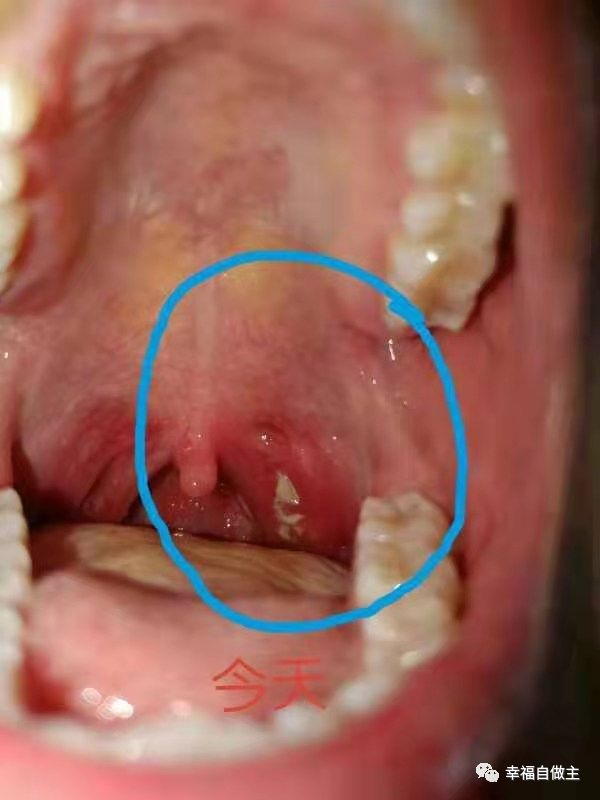

按推第一天

按推第二天

按推第三天

按推第四天

第5天早上醒来,女儿高兴了:“妈妈,嗓子没有那么难受了,扁桃体的溃疡处变小了”,继续一天撒姜粉五次左右,喝淡姜汤,刘学长给按推头部枕骨下缘,同时也埋沙温敷。

第6天继续,溃疡处小了七八成,基本不疼了。第七天基本上痊愈,撒姜粉两三次,坚持喝姜汤和温敷,饮食也正常了。